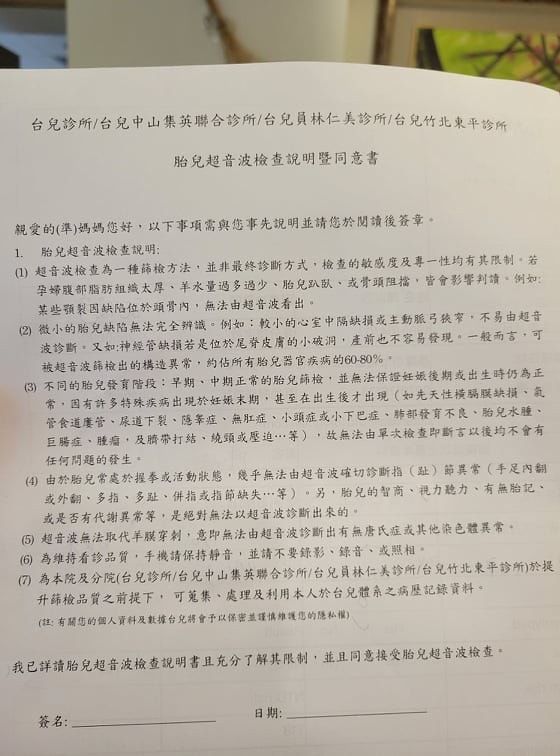

開始做檢查之前

也是會填寫一些資料

基本流程的概念